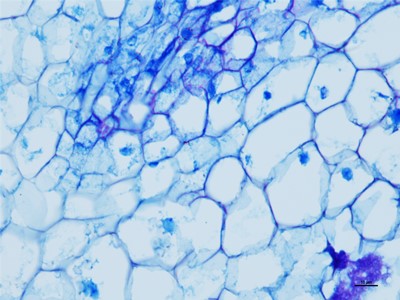

我们要在显微镜底下观察细胞的时候,就得把组织和细胞以及需要观察的东西切片,这些就得控制在厚度大概在1-10微米,这个厚度是最好观察物质的,如果没有在这个厚度之间的切片基本在观察就没有什么颜色。下面陕西依科生物技术有限公司针为大家介绍HE染色的具体操作步骤。

HE染色是基本病理的染色技术,HE染色是病理医生可以正确判断的唯一准则,首先在做实验的时候要准备乙醇、冰丙酮、苏木精染液、伊红染液、二甲苯、重庆中性树胶、培养瓶、培养皿、盖玻片、载玻片、显微镜等一些器材。首先将重庆石蜡切片脱蜡然后在将切片放进二甲苯无水乙醇,酒精,然后切片在放进伊红染色液中染色,然后就是将切片放入酒精和无水乙醇、二苯甲,脱水然后将切片拿出晾干,然后在封片。然后在用显微镜观察,图像采集。我们在做HE染色的实验时要注意以下细节,首先是脱蜡时要保持干净,已经苏木精染色的时间。以上就是HE染色的操作流程。